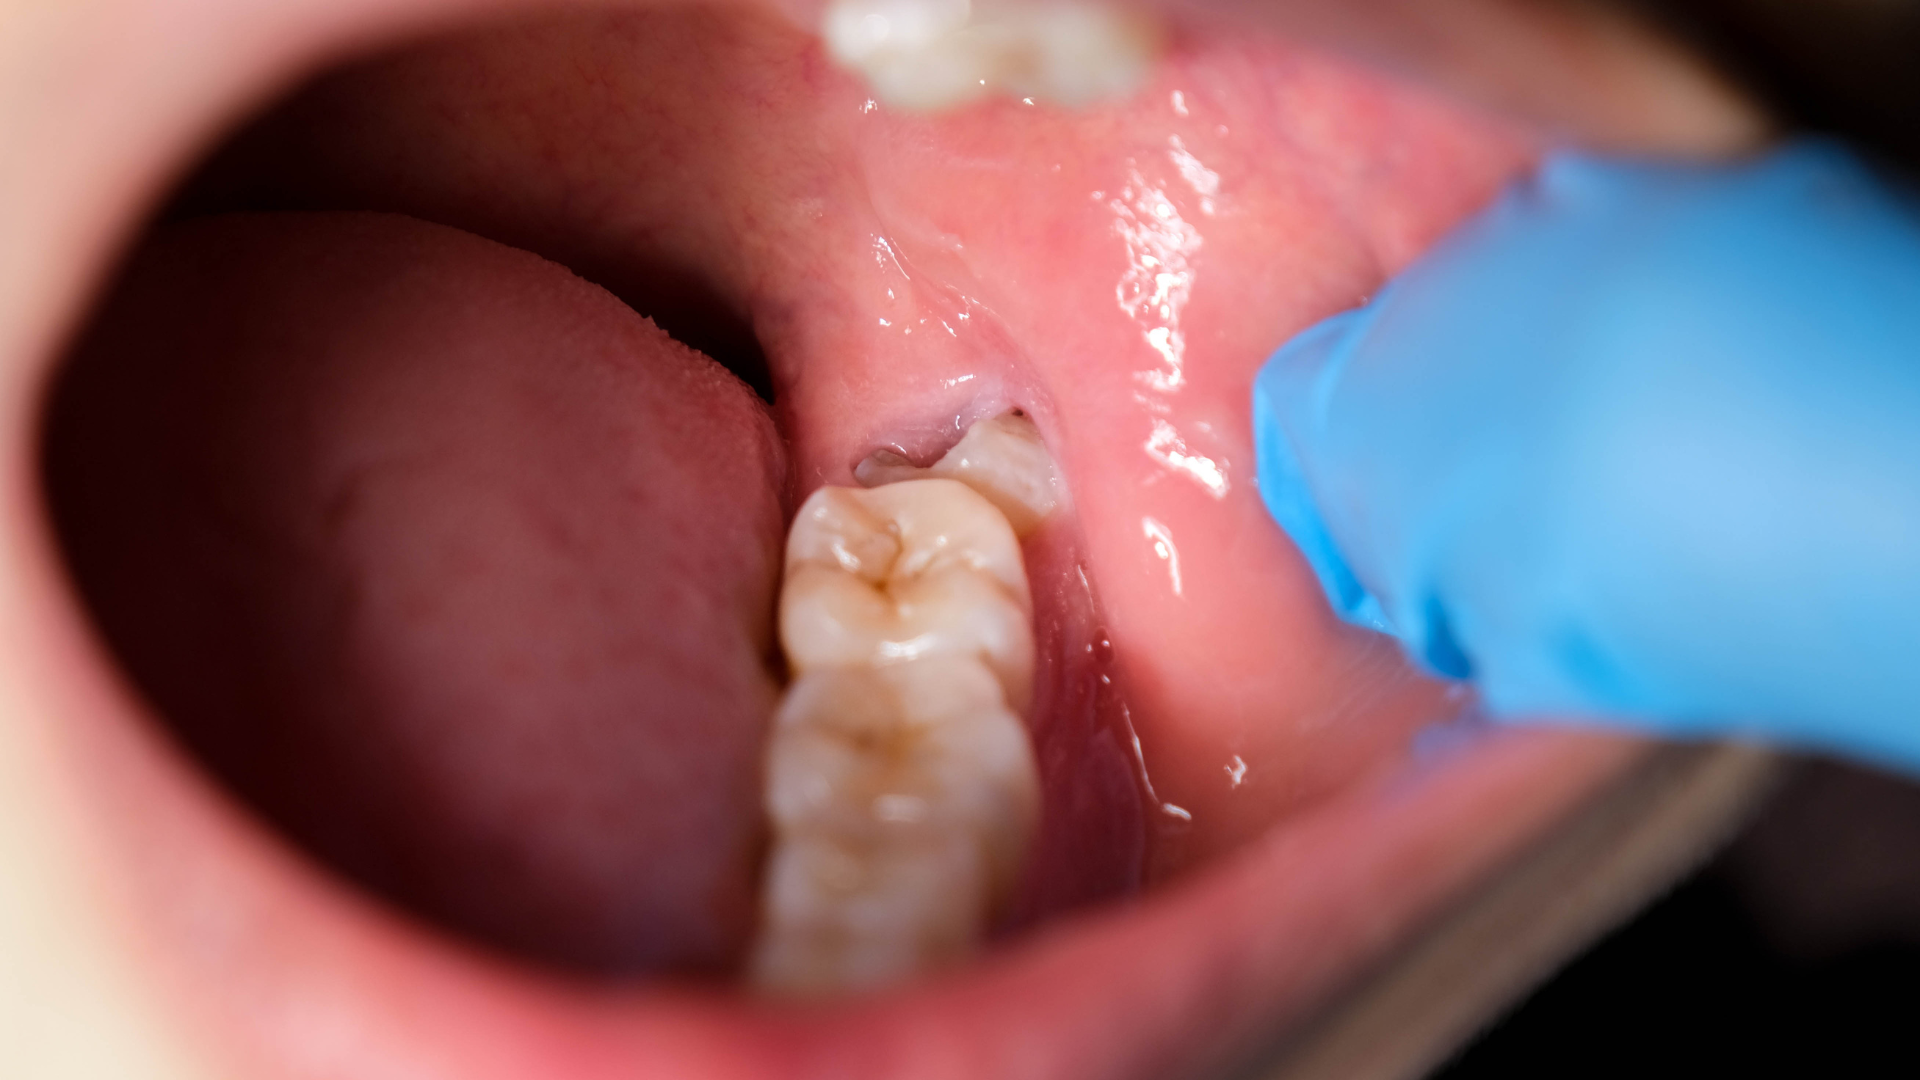

Không phải lúc nào răng khôn cũng mọc lộ rõ. Tuy nhiên, bạn có thể nhận thấy một số biểu hiện khi răng khôn mọc lệch đứng:

- Đau hoặc nhức vùng hàm trong cùng: Dai dẳng hoặc tăng khi nhai.

- Sưng, viêm nướu quanh răng: Nướu trùm dễ đỏ, chảy máu khi chải răng.

- Hôi miệng: Do thức ăn kẹt lại, vi khuẩn phát triển.

- Khó há miệng hoặc cứng hàm buổi sáng.

- Sốt nhẹ, nhức đầu trong đợt viêm nướu cấp.

Khi thấy nướu vùng răng hàm cuối dễ kích ứng, chảy máu lặp lại, bạn nên đặt lịch thăm khám răng miệng để xác định tình trạng sớm.